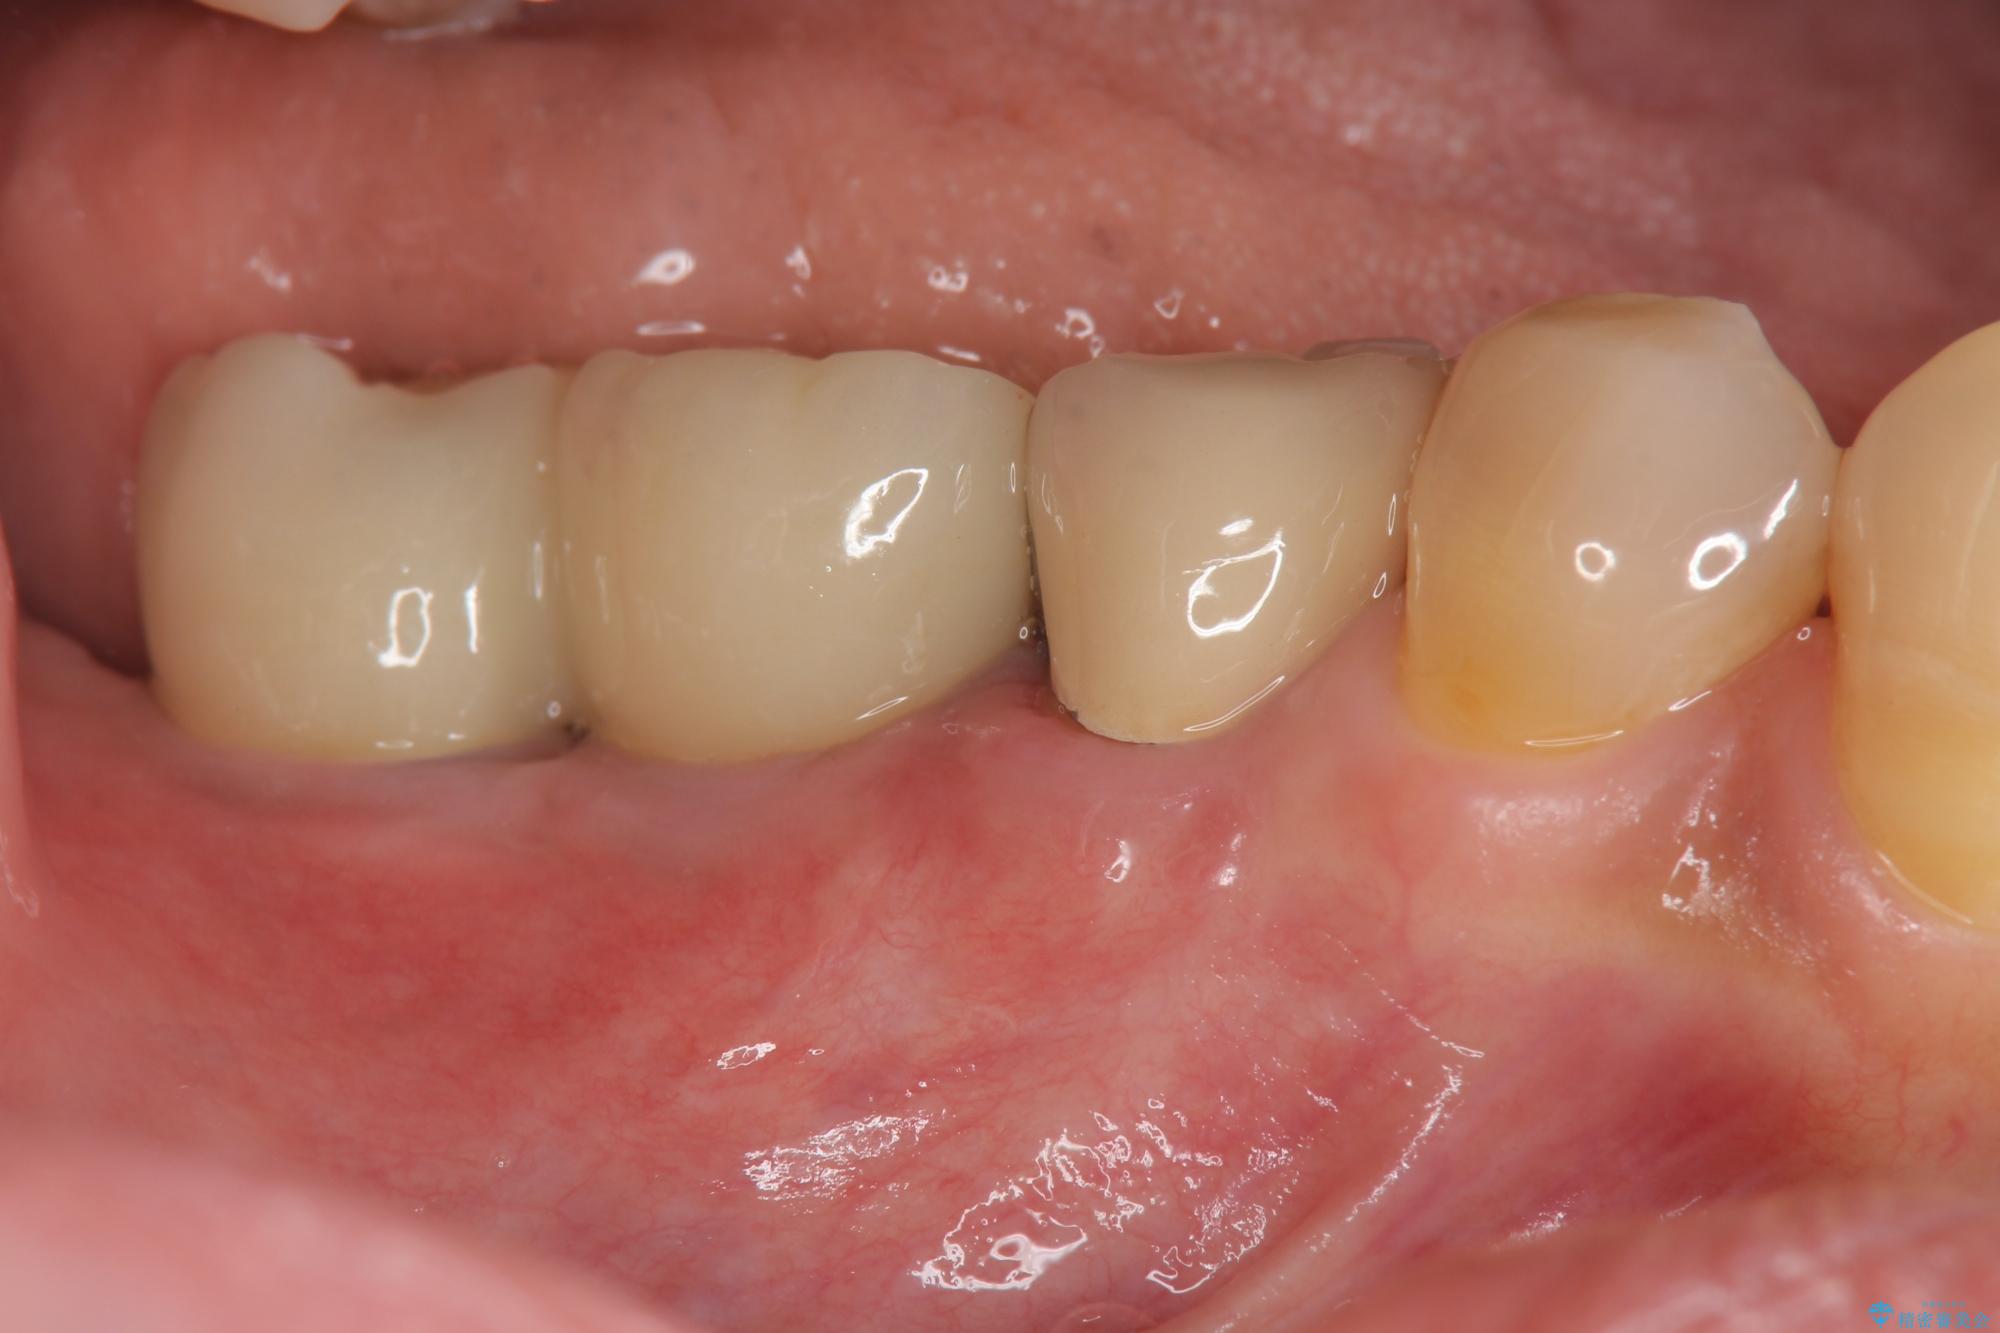

治療前

奥歯から膿のにおいがする インプラントによる機能回復 治療前画像 奥歯から膿のにおいがする インプラントによる機能回復 治療前画像 奥歯から膿のにおいがする インプラントによる機能回復 治療前画像 奥歯から膿のにおいがする インプラントによる機能回復 治療前画像 奥歯から膿のにおいがする インプラントによる機能回復 治療前画像 奥歯から膿のにおいがする インプラントによる機能回復 治療前画像